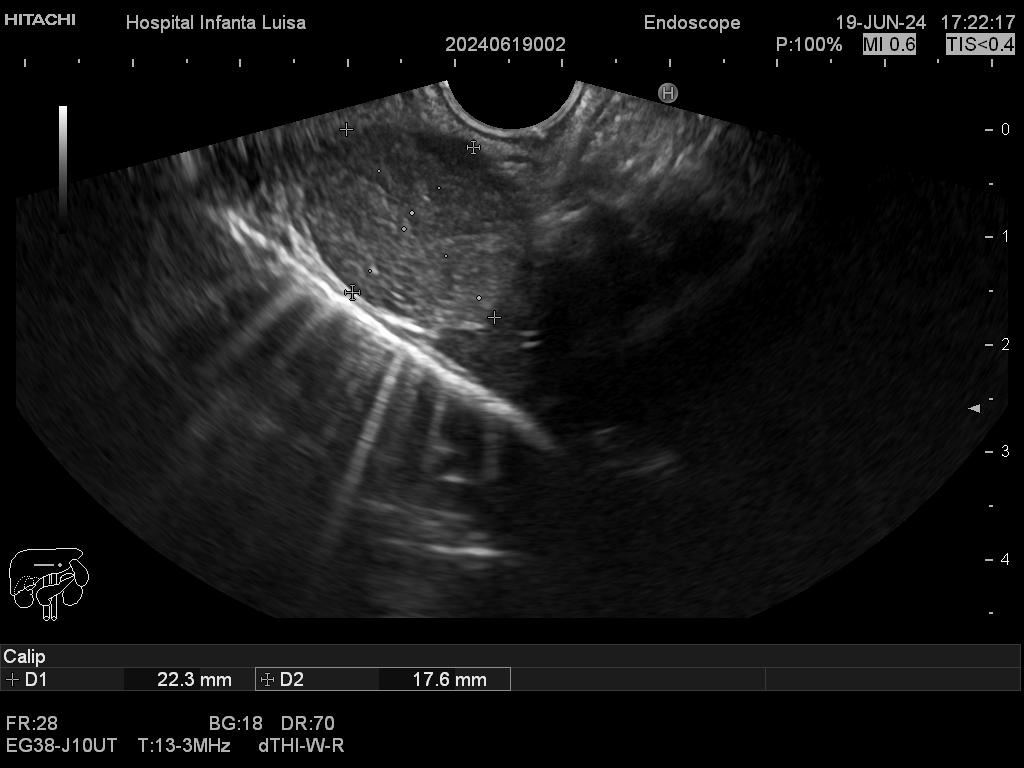

Mediante dicha exploración se explora minuciosamente los tramos mencionados, permitiendo valorar distintas patologías como lesiones propias de la pared de estos órganos (determinado su profundidad y extensión), o lesiones que quedan en órganos anexos, pero por fuera, de ahí la importancia de la visualización ecográfica, como páncreas, mediastino, hígado, diferentes adenopatías o masas indeterminadas previamente, entre otros.

Igualmente, es una técnica básica hoy día en el estudio de todo tipo de lesiones pancreáticas, en la determinación de formaciones subepiteliales esofágicas, gástricas (más frecuentes) o duodenales, o en el estadiaje de patología tumoral a estos niveles. La Ecoendoscopia permite la toma de biopsias a estos niveles, con control endoscópico y ecográfico, siendo una técnica de gran rentabilidad diagnóstica y seguridad.